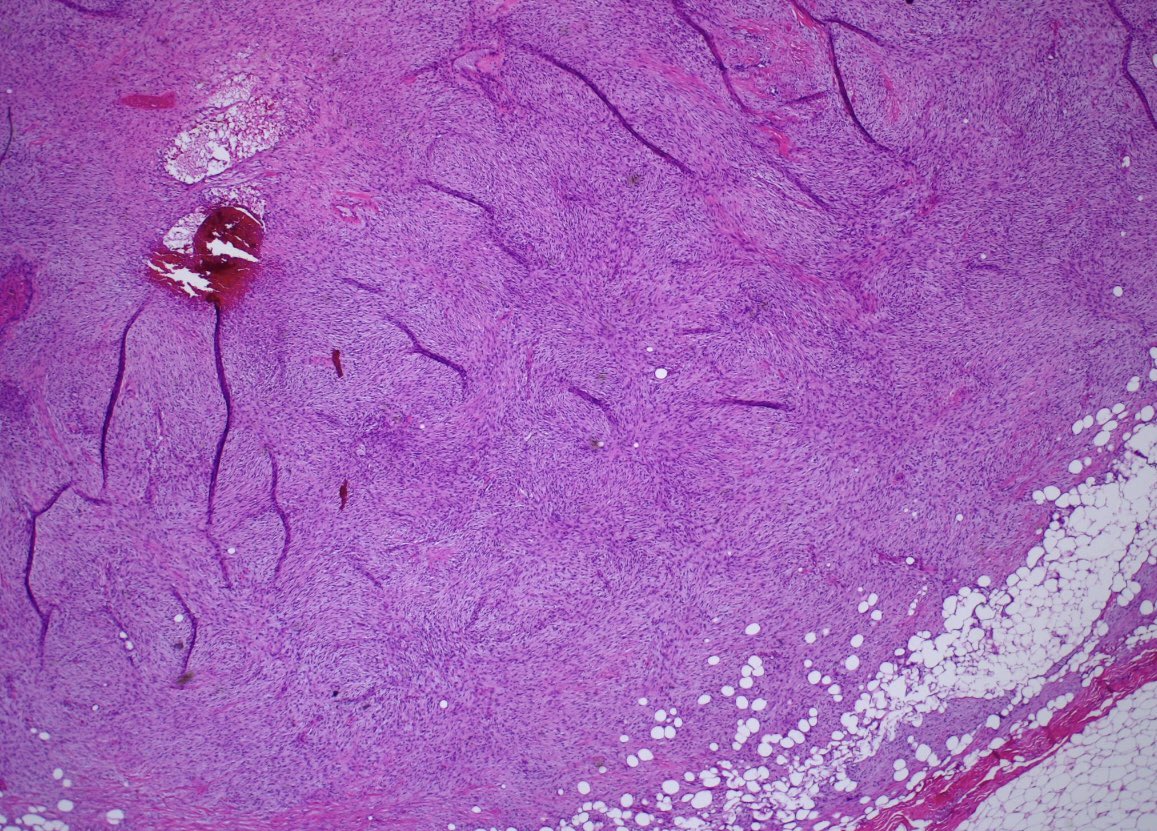

Clinicopathologic, immunohistochemical and genomic characterization of urothelial carcinoma with myxoid and chordoid features